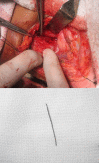

Accidental ingestion of foreign bodies is common in ENT practice. A very small number of ingested foreign bodies perforate the esophagus and even a smaller fraction of extra mucosal migration penetrates into the soft tissues of the neck. Most cases reported in the literature involve fish bones. If left untreated, they may result in life threatening complications. This case presents a patient with a metallic foreign body (metal wire) in the esophagus which migrated extraluminally into the prevertebral muscle of the neck and describes the difficulties encountered in removing the migrated foreign body. Intra-operative radiography using two metallic pointers was used to locate the exact position of the foreign body during exploration of the neck.